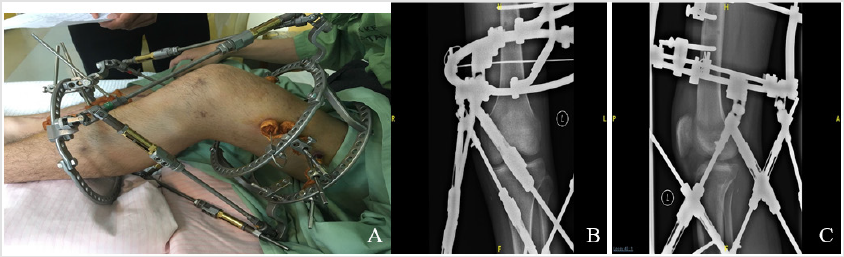

Both patients were satisfied with their outcome. Good reductions of their knee joints were obtained as per radiographic evidence. Resulting knee functions were graded “fair” for the first patient and “good” for the second patient based on Lysholm Knee Scoring Scale. Apart from mild pin tract infections no other complications occurred during their course of treatment (Figures 1 & 2, Table 1).

Figure 2: Post reduction knee photograph and plain radiographs of the same patient. (A) The photograph demonstrates gross anterior tibial translation compared to Figure 1 A. Ortho-SUV frame is currently in passive range of motion training mode. B. AP view and C. lateral view plain radiographs showing reduced knee joint.